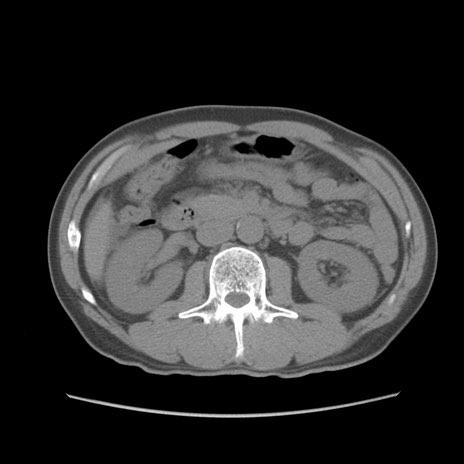

症例56 CT(横断像)

脂肪ウインドウ